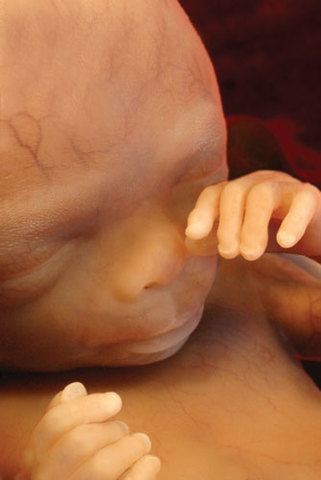

• A magzat fejlődése a nyolcadik hónapban

A magzat fejlődése a nyolcadik hónapban

A tüdő fejlődése lassan eléri azt a fokot, amikortól önállóan is képes a légzésre. A zsírpárnák felhalmozódása folytatódik, a magzat egyre jobban hasonlít az újszülöttre.